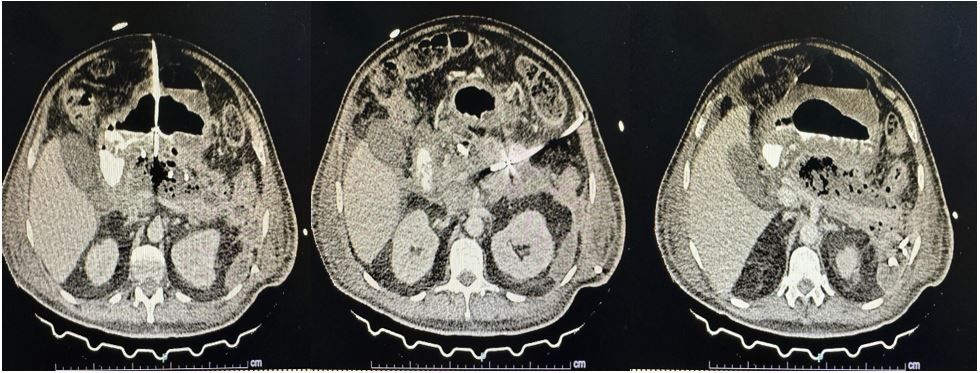

Evolucionó con inestabilidad hemodinámica, por lo que se le cambió la antibioticoterapia a meropenem más vancomicina y se definió tratar las colecciones por el Servicio de Radiología Intervencionista con colocación de catéteres percutáneos guiados por TC a nivel transabdominal, transgástrico y axilar (Fig. 2), realizándose lavados diarios con solución salina.

Figura 2. A y B. TC de abdomen simple; colocación de catéteres percutáneos. C y D: reconstrucción 3D donde se evidencia la posición de los catéteres implantados.